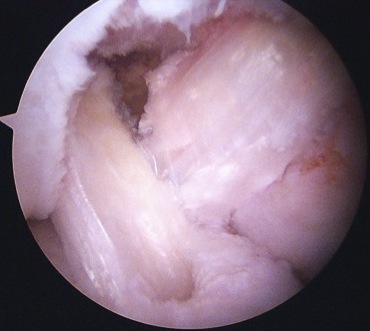

PCL Tibial Tunnel

Change to 70o scope

- under vision clear PCL facet

- release posterior capsule from bone (visualise popliteus muscle)

- release posterior speptum (attaches to PCL, and divides knee into posteromedial and posterolateral)

- PCL guide 65o angle

- tibial guide placed just lateral to crest to ensure room for more medial ACL tunnel

- place on posterior facet, slightly lateral

- check on fluoroscopy on PCL facet

- protect guide wire with curette or switching stick via PM cannula

- carefully ream 10 mm tunnel

- clear tunnel entrance of debris